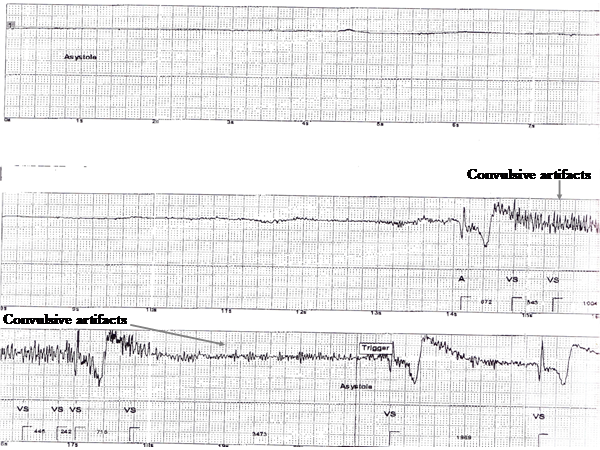

Figure 3

Prolonged asystole followed by a convulsive activity.

Figure 4

Tracing reveals return of patients' rhythm to Sinus.

A thirty four year old woman was referred to our syncope and autonomic disorder center for evaluation of recurrent unexplained periods of transient loss of consciousness (TLOC) associated with convulsive activity. The episodes would come on suddenly while sitting or standing with little or no prodrome. She would abruptly lose consciousness and fall to the floor. Bystanders reported her to be pale and ashen in color. Witnesses reported that during episodes she would display tonic-colonic like convulsive activity lasting from 1-5 minutes associated with urinary incontinence. The loss of consciousness could last for 30 to 45 minutes. Afterwards the patient was confused and fatigued for the remainder of the day. The patient had undergone multiple evaluations including, 12 lead electrocardiograms, echocardiography, stress testing, tilt table testing and prolonged holter and event monitoring, all of which were unremarkable. Repeated electroencephalograms (including a prolonged inpatient monitoring) were inconclusive and empiric therapy with multiple anti- seizure medications did not alter the frequency or severity of her TLOC. She was labeled as having either refractory epilepsy or conversion disorder. After presentation to our center she underwent placement of an implantable loop recorder (ILR). She later suffered one of her typical TLOC episode associated with witnessed convulsive activity. A download of the device demonstrated that concomitant with the episode of TLOC the ILR had recorded a periods of complete heart block followed by a prolonged periods of asystole, with artifacts consistent with convulsive activity was noted. Prolonged periods of asystole have been reported to result in convulsive activity that may be misdiagnosed as being due to epilepsy (1,2,3). The patient then underwent permanent pacemaker implantation with complete resolution of her TLOC episodes.

This case graphically illustrates the utility of the ILR in establishing the cause of recurrent unexplained TLOC. In addition the tracing demonstrates an interesting sequence of complete heart block followed by prolonged asystole that resulted in TLOC with convulsive activity. Prolonged asystole has been reported to cause abrupt onset, convulsive episodes with prolonged loss of consciousness that at times can be misdiagnosed as epilepsy (1, 2, 3). An ILR can be invaluable in identifying these patients and facilitating prompt therapy (3).